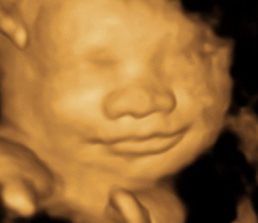

A Little Insight is proud to announce that we now offer 8K technology. This is the most realistic & amazing view of your unborn baby.

A Little Insight is an elective ultrasound center dedicated to providing a private experience that focuses on you and your baby, and we believe that every parent deserves to maximize their prenatal experience. Our 3D/4D & 5D ultrasounds provide an opportunity for you to see your baby not only in still image but in real-time motion. Why wait until your baby is born to celebrate his/her life?

A Little Insight 3D/4D/5D Ultrasound is unique because we truly offer the finest 3D/4D & 5D prenatal experience available. We combine cutting-edge technology with a family theater environment to bring you incredible images of your unborn baby in the womb. Best of all, we offer an unparalleled bonding experience that you and your family can cherish for a lifetime!